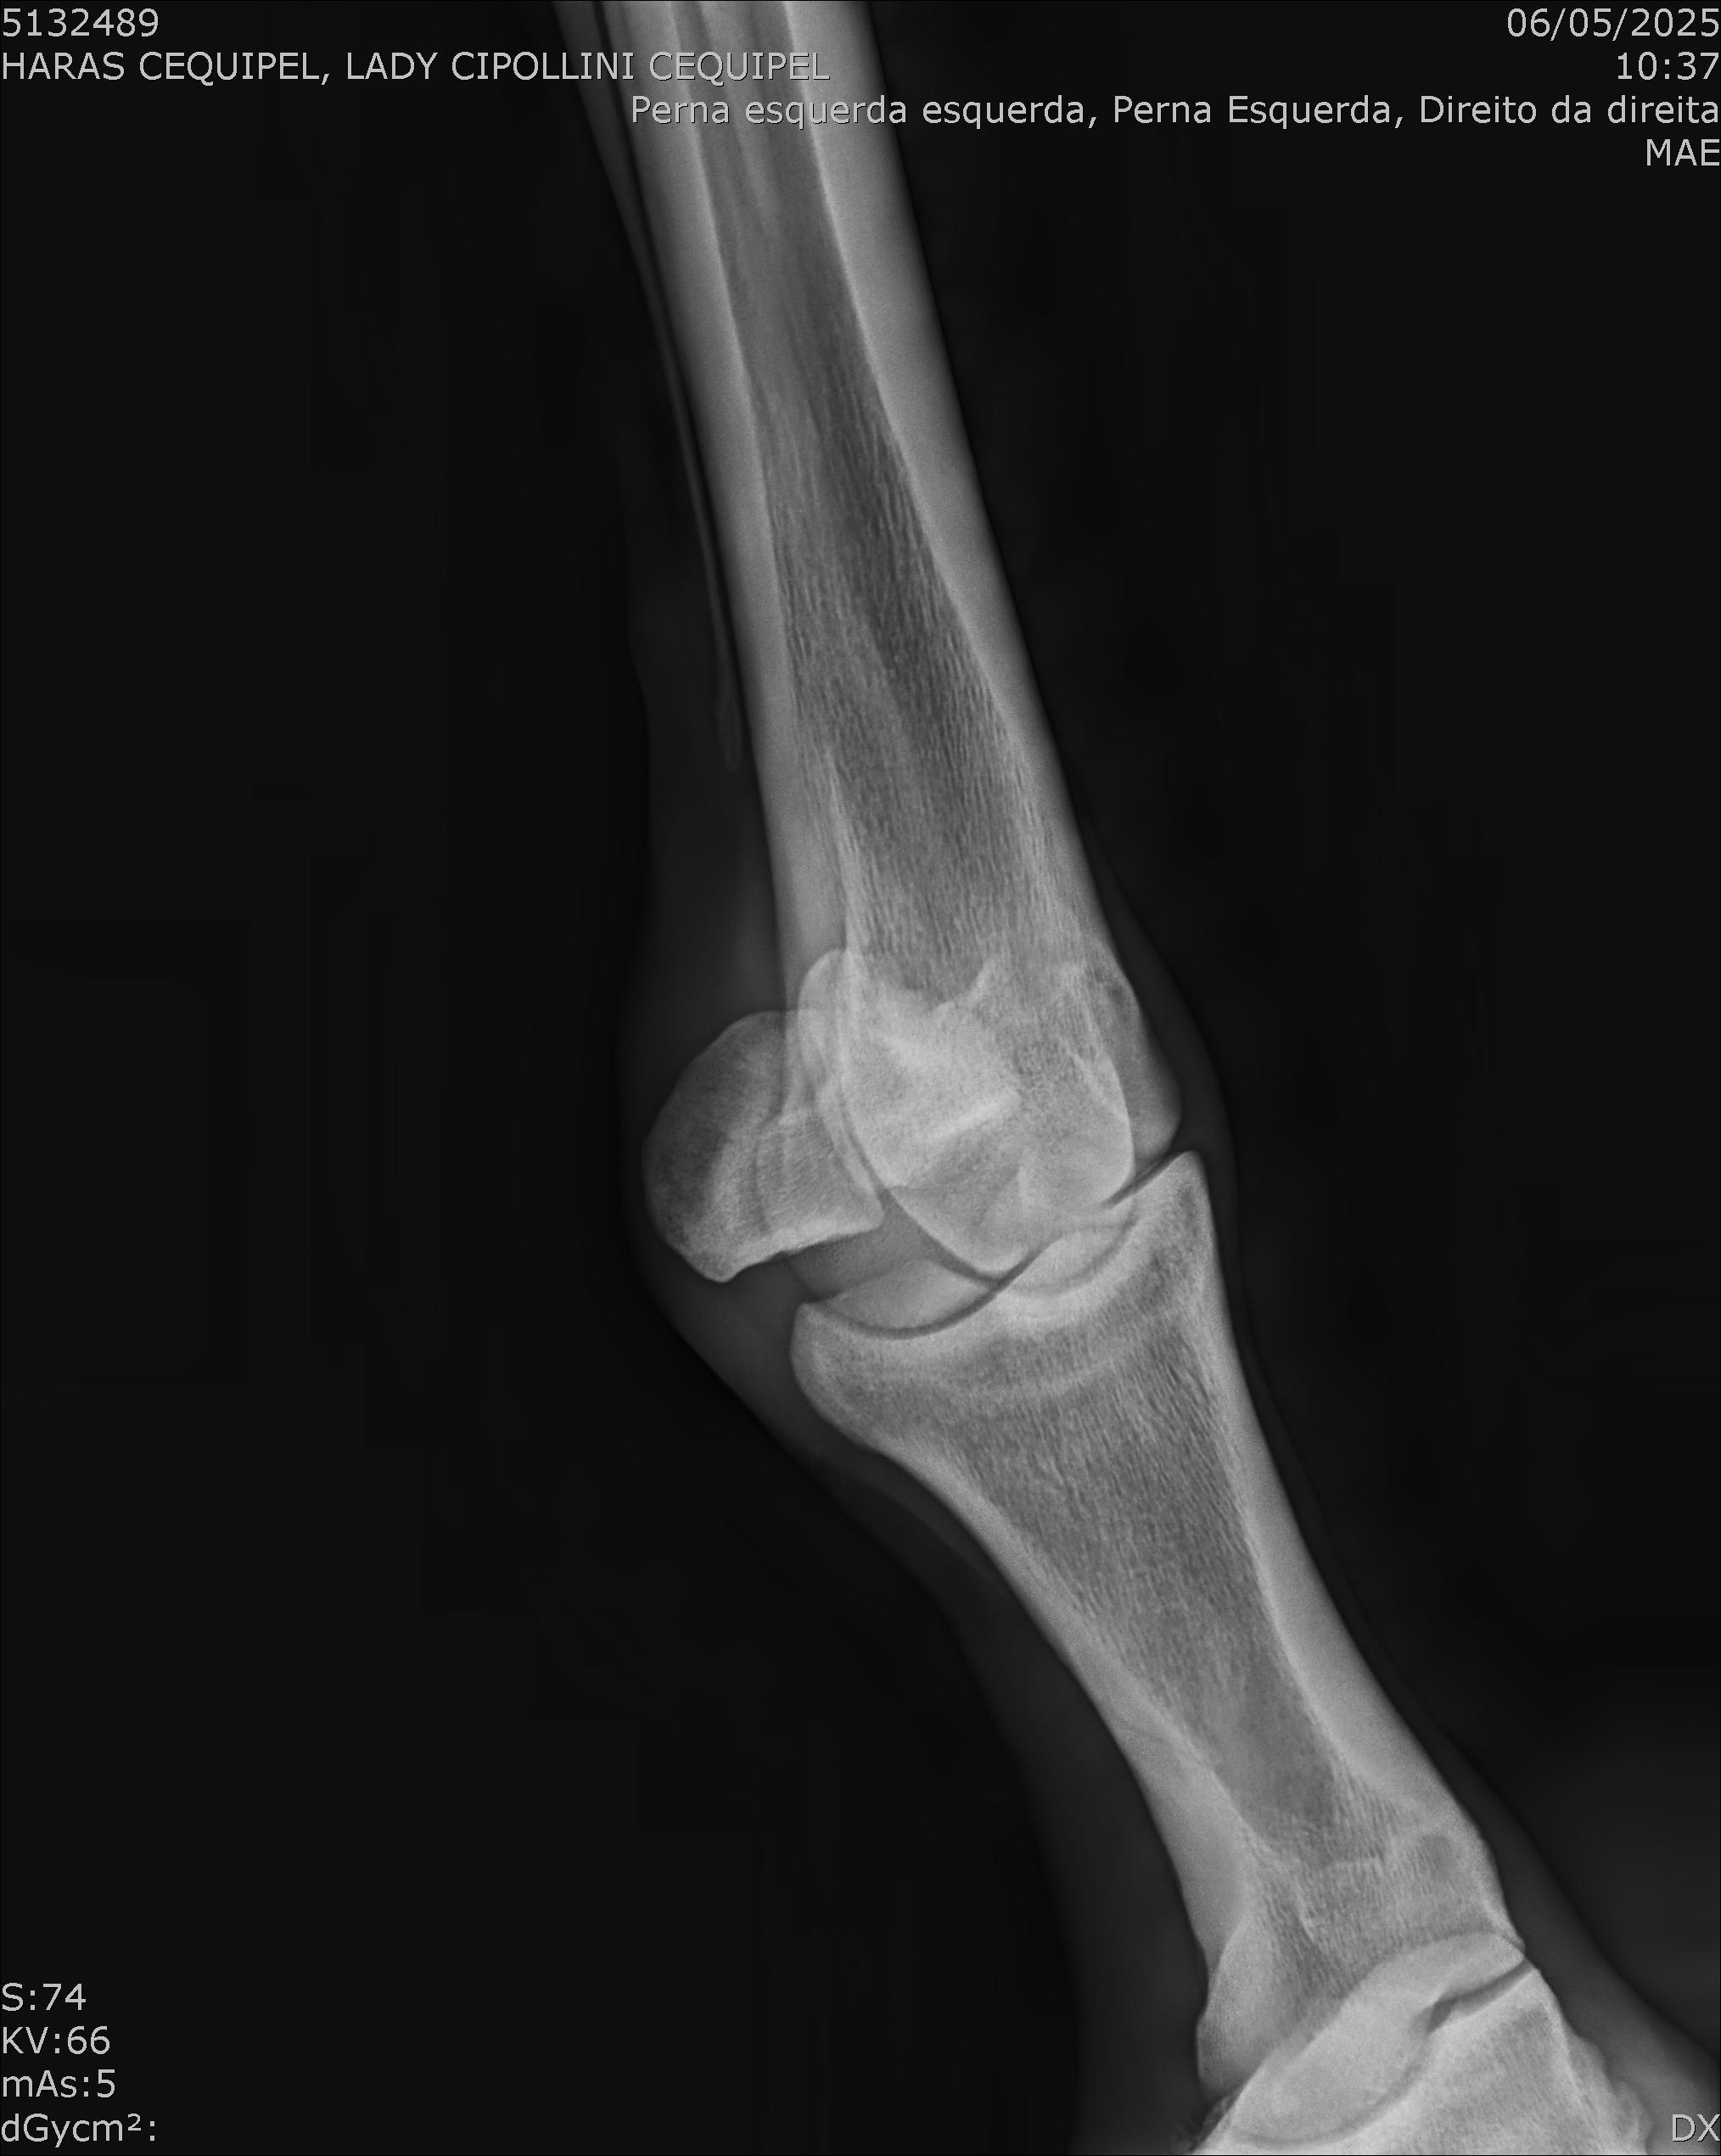

:: RAIOS-X DO LOTE